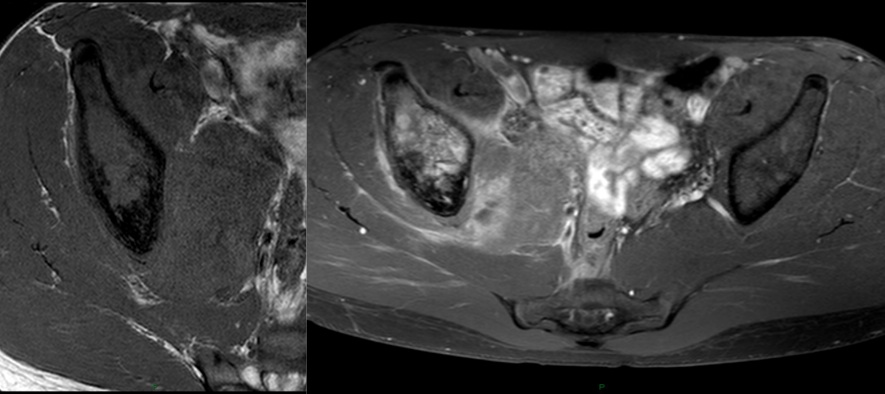

Figure 4 for case Ewing Sarcoma

Figure 4

Figure 5 for case Ewing Sarcoma

Figure 5